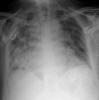

Fibrosis pulmonar. ICC.

Neumonia basal derecha.

Neumonía basal derecha.

EAP